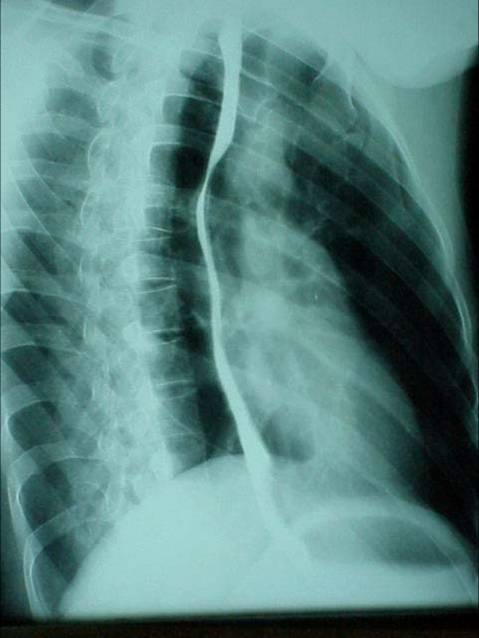

照片名称:左胸腔包裹积液